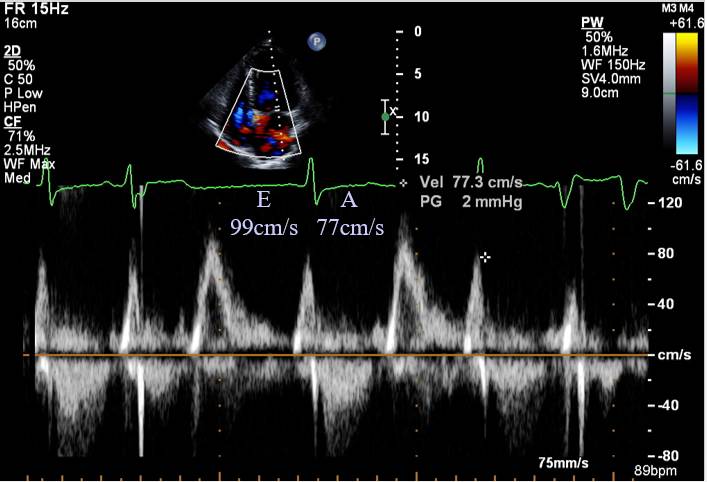

HFpEF + 房颤 导管消融

心室率控制

随访

◆消融后心功能正常,阵发房扑

◆3年后因阵发房扑行第二次消融

◆随访9年

SHFM 消融前(上)后(下)

[19]